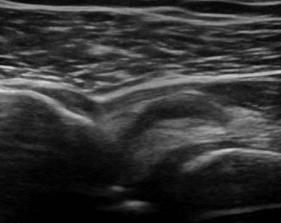

Rotator Cuff Tear

Supraspinatus Tear